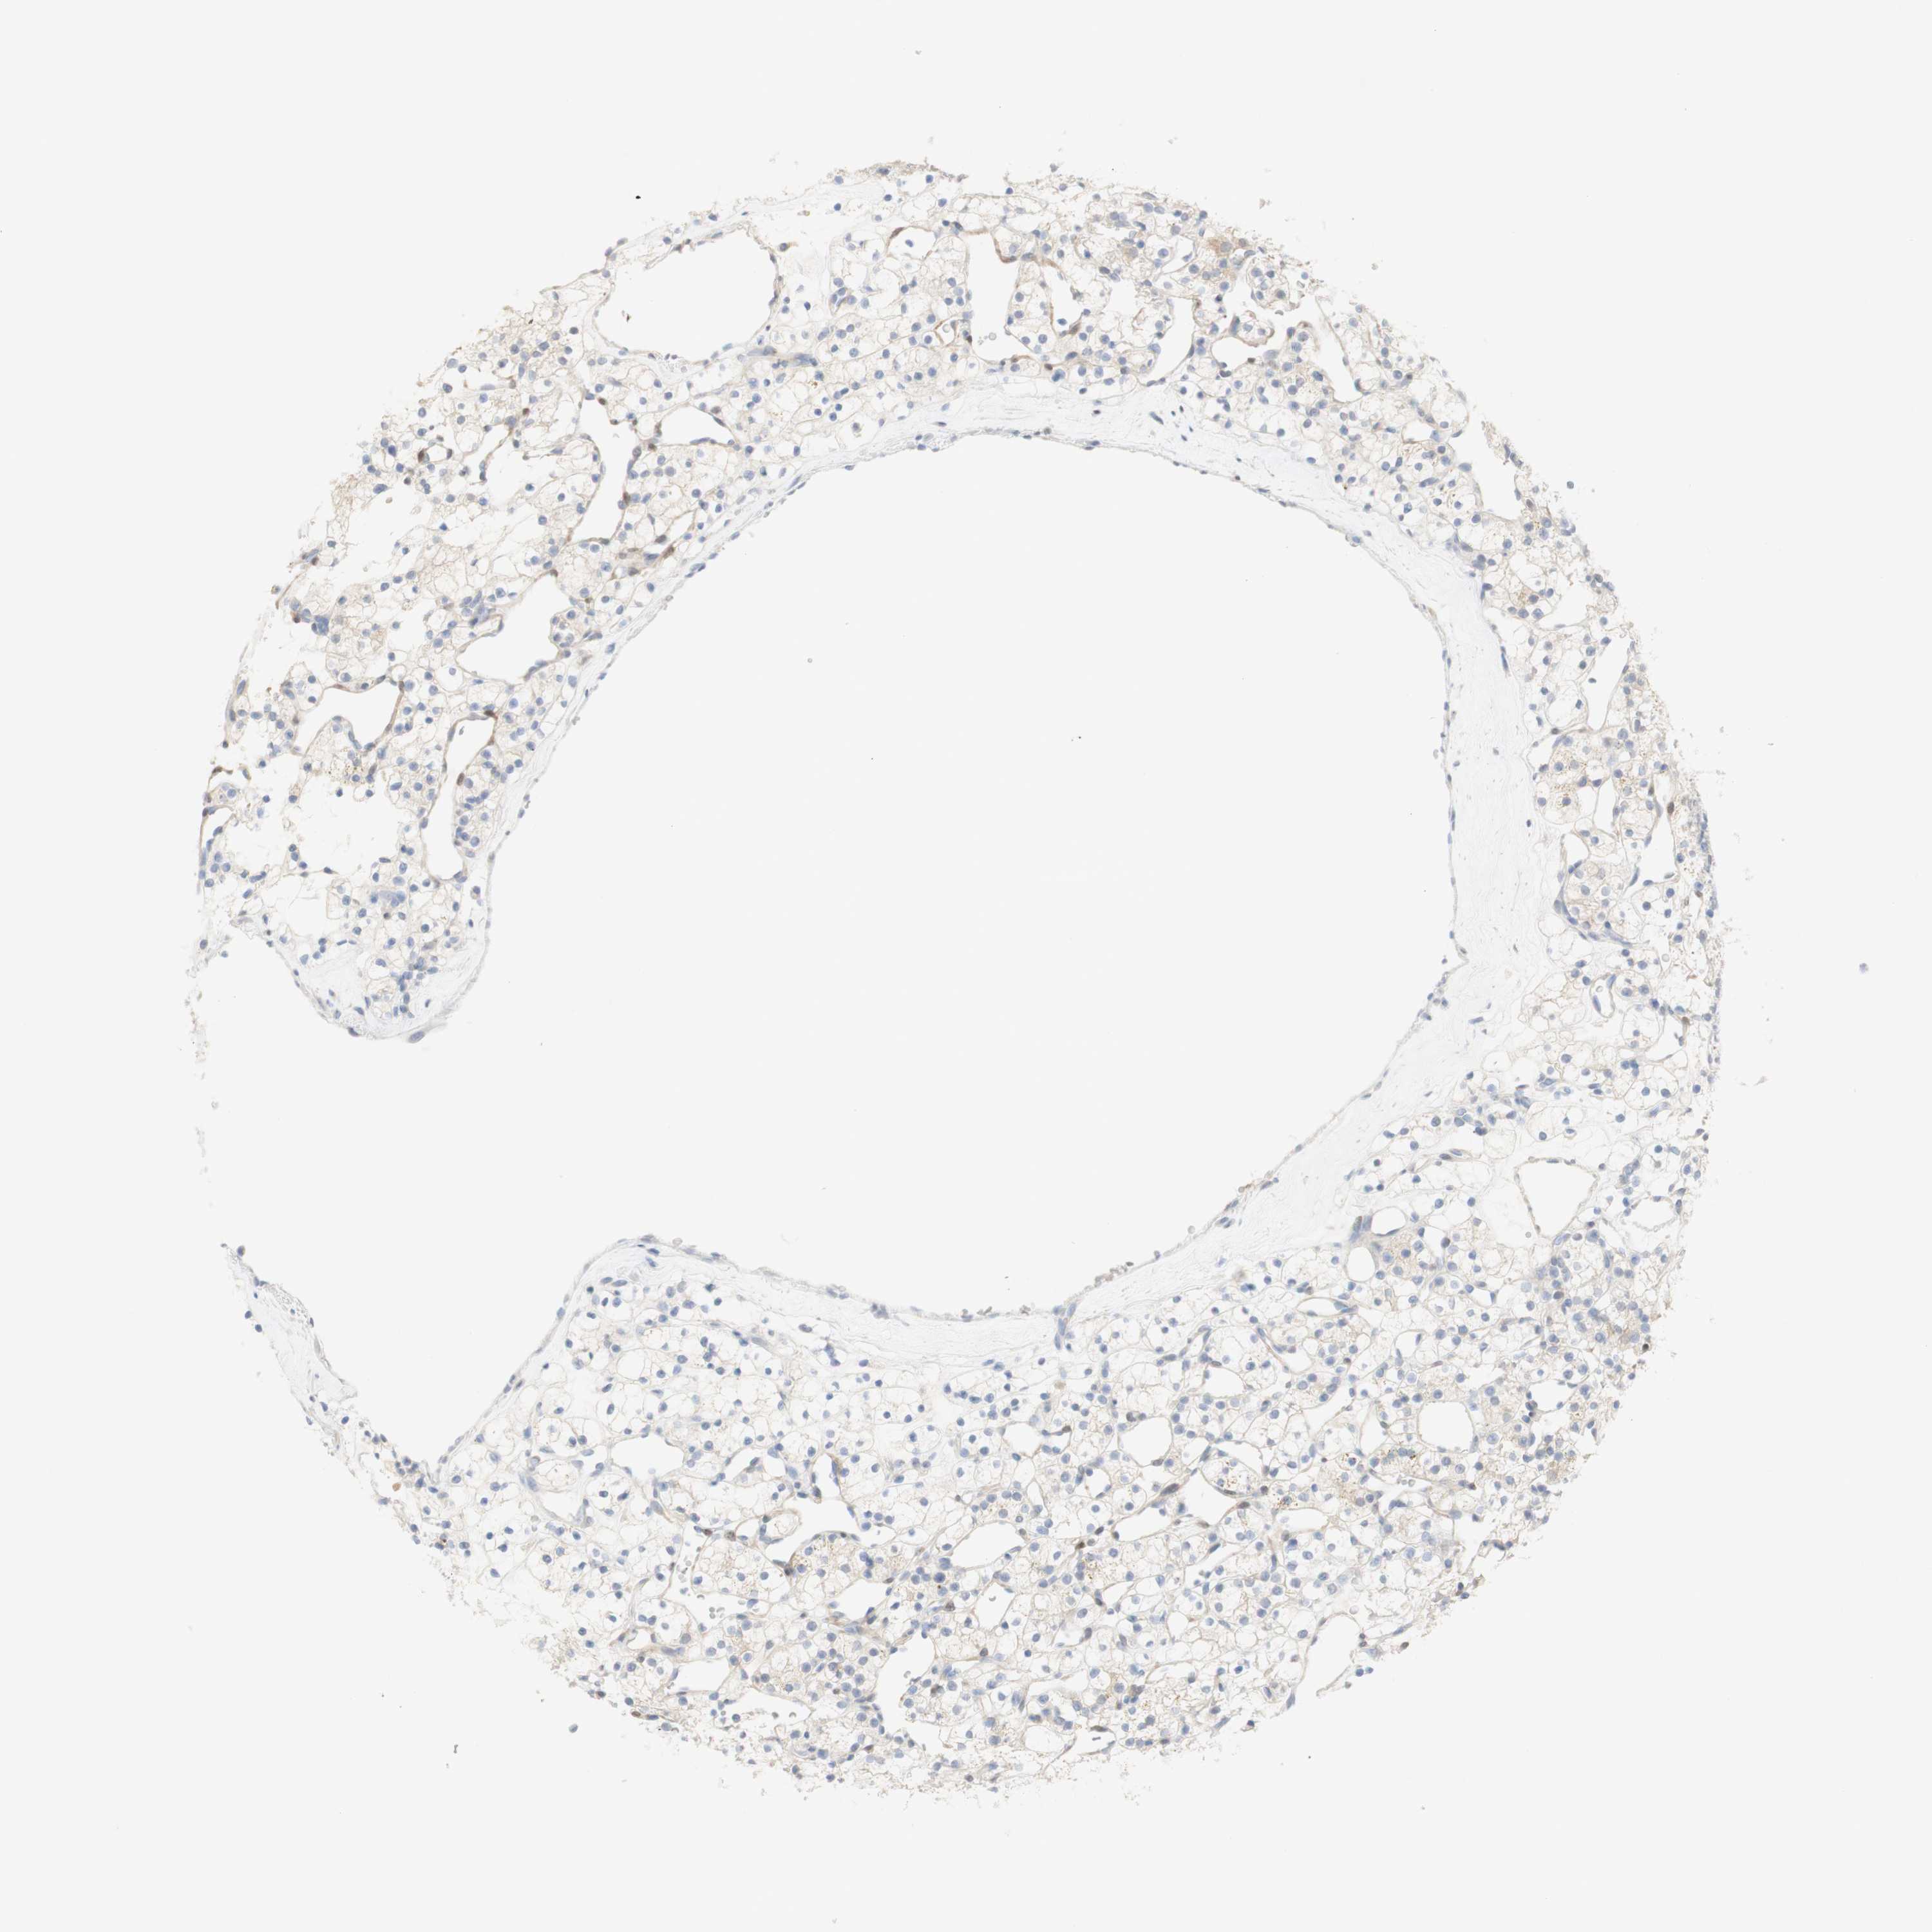

KIDNEY RENAL CLEAR CELL CARCINOMA (VALIDATION) - Interactive survival scatter ploti

The Survival Scatter plot shows the clinical status (i.e. dead or alive) for all individuals in the patient cohort, based on the same data that underlies the corresponding Kaplan-Meier plots. Patients that are alive at last time for follow-up are shown in blue and patients who have died during the study are shown in red.

The x-axis shows the expression levels (FPKM) of the investigated gene in the tumor tissue at the time of diagnosis. The y-axis shows the follow-up time after diagnosis (years). Both axes are complimented with kernel density curves demonstrating the data density over the axes. The top density plot shows the expression levels (FPKM) distribution among dead (red) and alive patients (blue). The right density plot shows the data density of the survived years of dead patients with high and low expression levels respectively, stratified using the cutoff indicated by the vertical dashed line through the Survival Scatter plot. This cutoff is automatically defined based on the FPKM cutoff that minimizes the p-score. The cutoff can be changed by dragging the vertical line or by entering a cutoff value in the square labeled "Current cut-off".

Under the Survival Scatter plot the p-score landscape (black curve; left axis) is shown together with dead median separation (red curve; right axis). Dead median separation is the difference in median mRNA expression between patients who have died with high and low expression, respectively. It is calculated as follows: median FPKM expression of dead patients with high expression - median FPKM expression of dead patients with low expression. This is intended to aid the user in visually exploring custom cutoffs and the associated p-scores and dead median separation.

Individual patient data is displayed and can be filtered by clicking on one or more of the category buttons on the top of the page. Categories describing expression level and patient information include: high, low, alive, dead, female, male and tumor stages. The scale of the x-axis can be toggled between linear and log-scale by clicking on the "x log" button. Mouse-over function shows TCGA ID, patient information and mRNA expression (FPKM) for each patient.

& Survival analysisi

Kaplan-Meier plots summarize results from analysis of correlation between mRNA expression level and patient survival. Patients were divided based on level of expression into one of the two groups "low" (under cut off) or "high" (over cut off). X-axis shows time for survival (years) and y-axis shows the probability of survival, where 1.0 corresponds to 100 percent.

SELENBP1 is not prognostic in Kidney Renal Clear Cell Carcinoma (validation)

Best expression cut offi

Based on the FPKM value of each gene, patients were classified into two groups and association between prognosis (survival) and gene expression (FPKM) was examined. The best expression cut-off refers the FPKM value that yields maximal difference with regard to survival between the two groups at the lowest log-rank P-value. Best expression cut-off was selected based on survival analysis .

When clicking on this number, the vertical dashed line indicating cut-off, the interactive survival plot, and the Kaplan-Meier curve will be adjusted to show results based on the best expression cut-off.

: 16.79

Median expressioni

Median expression refers to the median FPKM value calculated based on the gene expression (FPKM) data from all patients in this dataset. When clicking on this number, the vertical dashed line indicating cut-off, the interactive survival plot, and the Kaplan-Meier curve will be adjusted to show results based on the median expression.

: N/A

Median follow up timei

Median follow up time refers to the median time (years) after diagnosis with this type of cancer, based on clinical data from all patients in this dataset.

P scorei

Log-rank P value for Kaplan-Meier plot showing results from analysis of correlation between mRNA expression level and patient survival.

N/A

5-year survival highi

5-year survival for patients with higher expression than the expression cutoff.

For melanoma and glioma, 3-year survival is shown.

5-year survival lowi

5-year survival for patients with lower expression than the expression cutoff.

TCGA RNA samplesi

RNA-seq data is reported as average FPKM (number Fragments Per Kilobase of exon per Million reads), generated by the The Cancer Genome Atlas (TCGA) .

Normal distribution across the dataset is visualized with box plots, shown as median and 25th and 75th percentiles. Points are displayed as outliers if they are above or below 1.5 times the interquartile range. FPKM values of the individual samples are presented next to the box plot.

Average pTPM 21.7

Number of samples 100